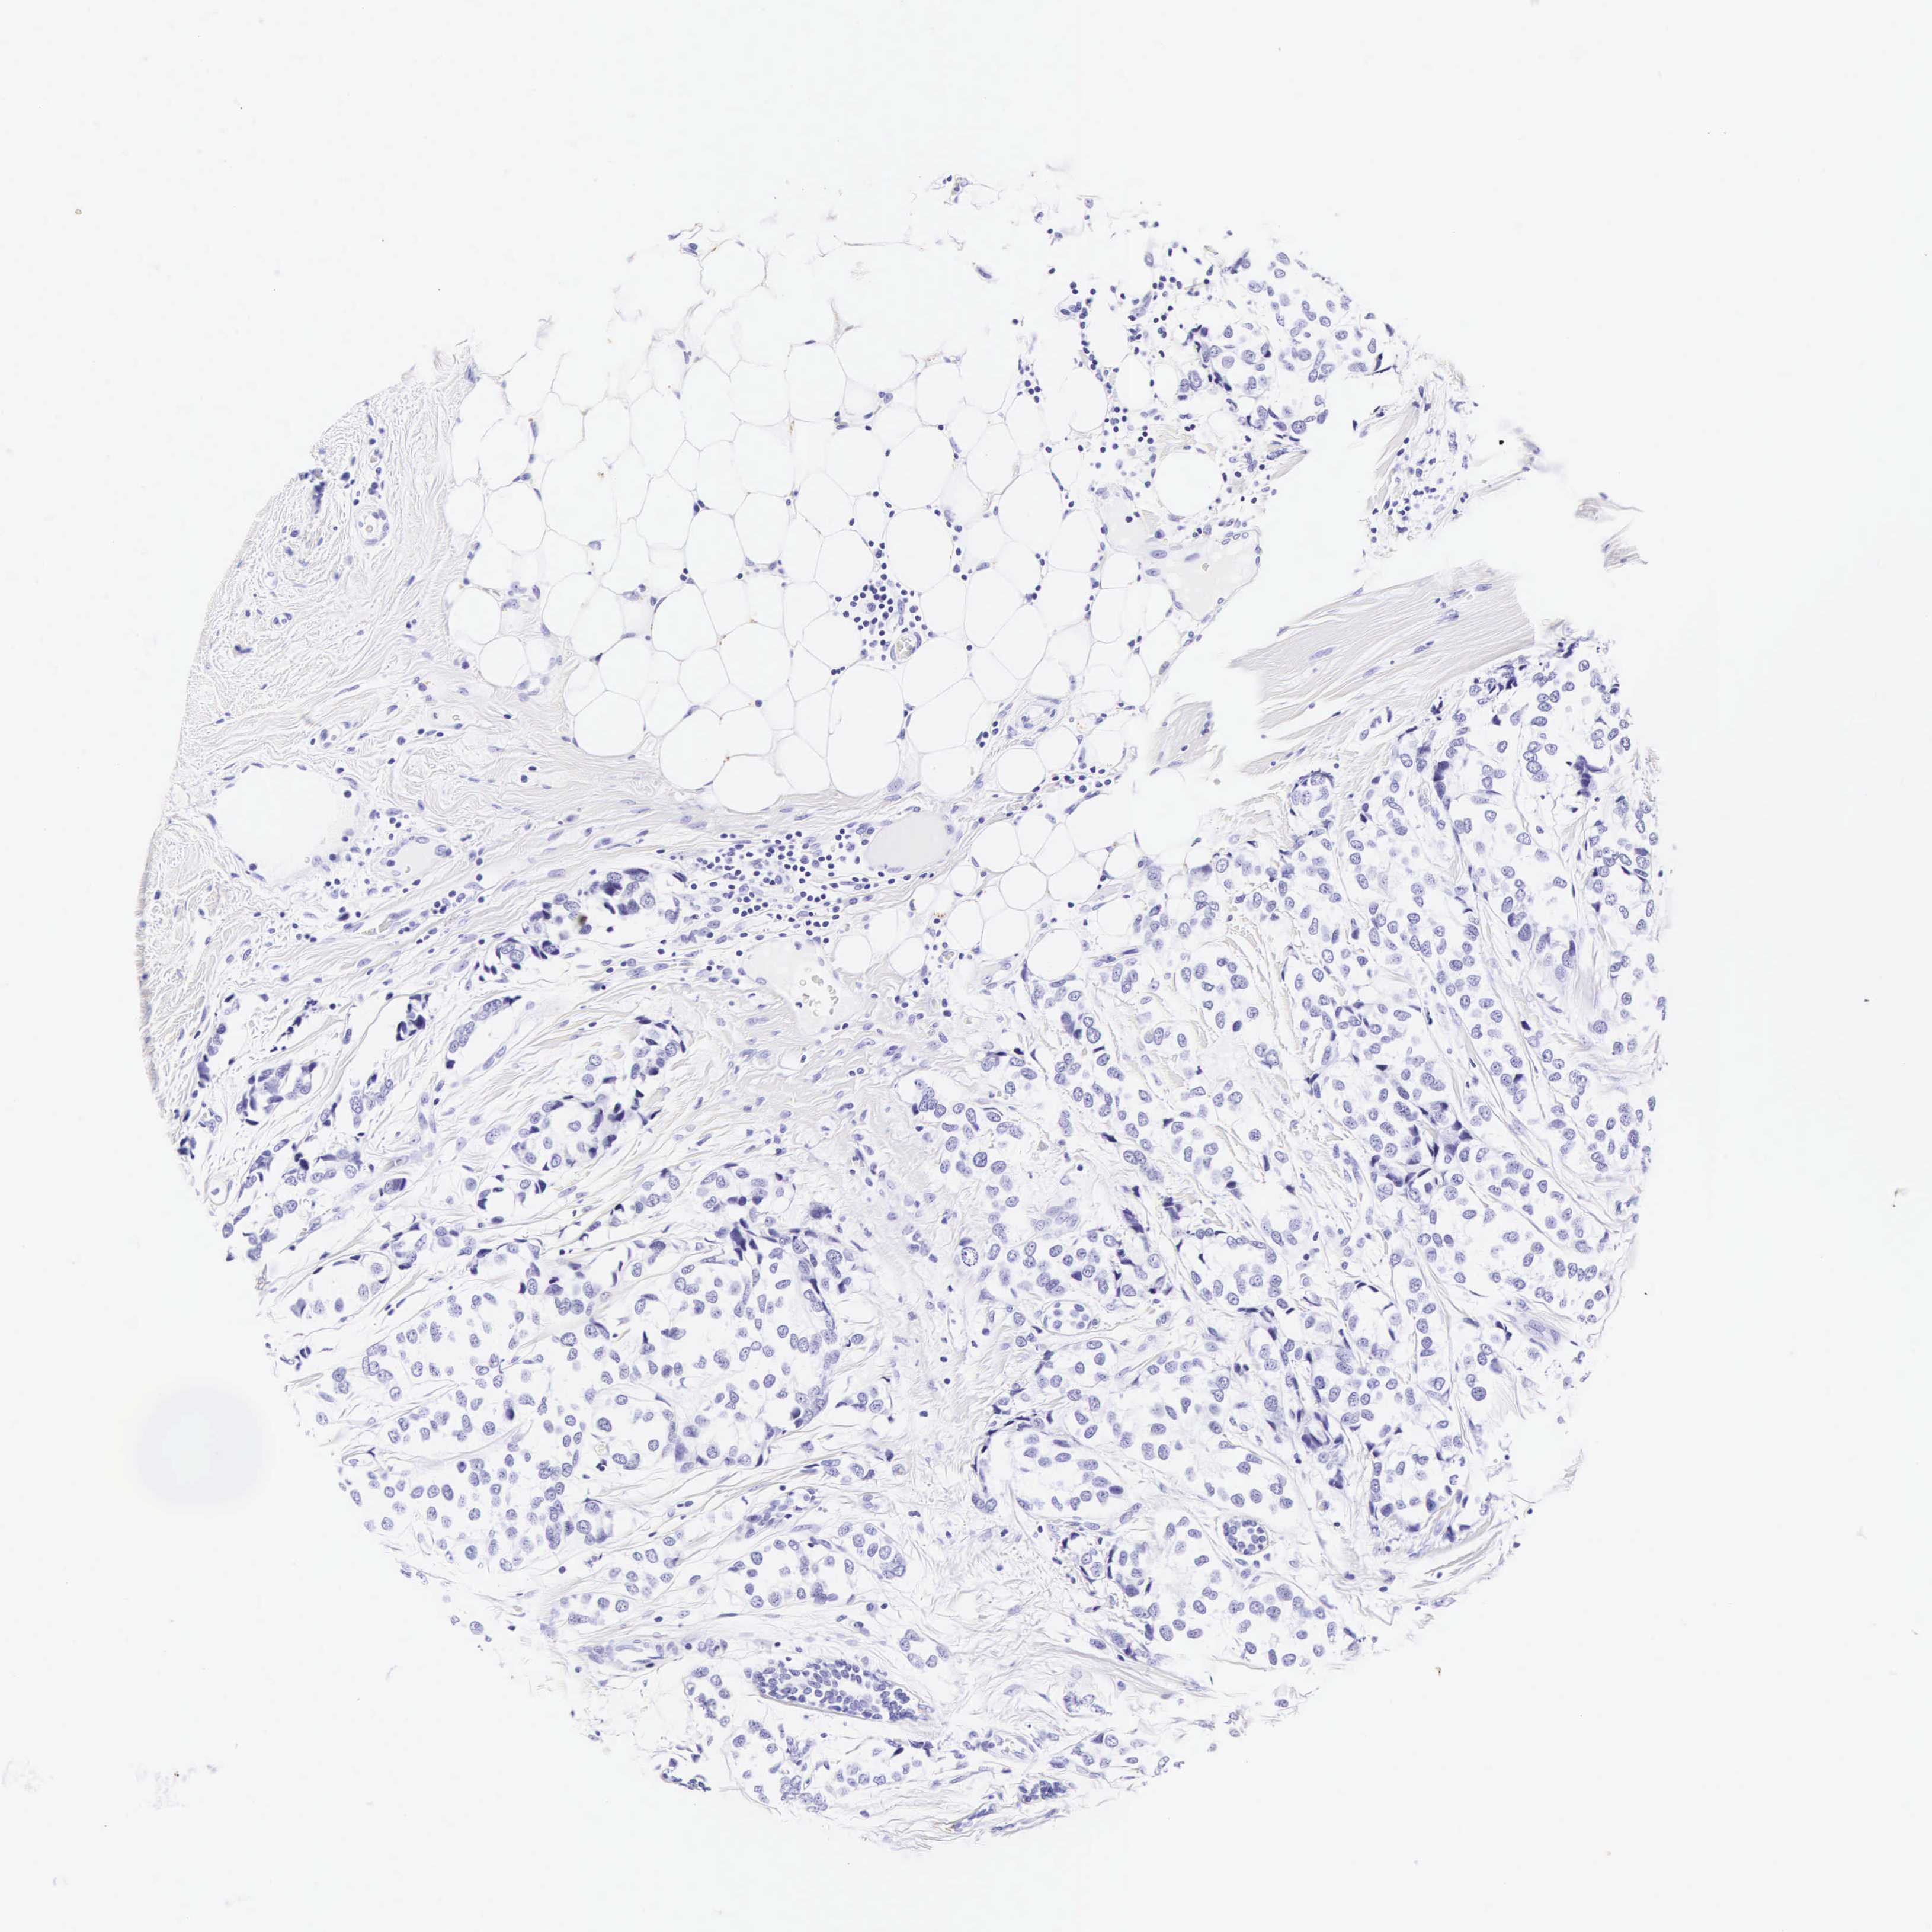

Breast cancer

Human cancer